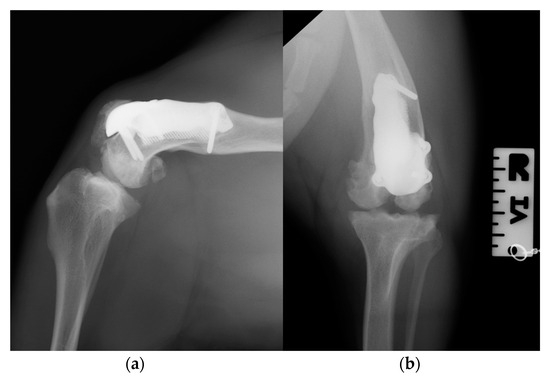

At the 3-month postoperative follow-up, the orthopedic, radiographic and tomographic examination were repeated. The patient showed a grade II right hind limb lameness (on a scale from 0 to IV) [19] (Video S3b). On stifle joint palpation and manipulation, crepitus persisted. The arthralgia and capsular ectasia decreased compared to the postoperative follow-up, and mild pain was elicited upon palpation of the patellar ligament. The estimated angle of extension and flexion of the right stifle was 150–90°, respectively. The radiographic and tomographic evaluations revealed the absence of implant-associated complications, such as implant loosening and migration, a thickening of the patellar ligament, signs of suspicious desmitis and mild osteoarthritic progression at the distal pole of the patella (Figure 11).

Figure 11. Three-month postoperative medio-lateral (a) and caudo-cranial (b) radiographs of the stifle joint showing the absence of implant-associated complications, such as implant loosening and migration, a thickening of the patellar ligament and mild osteoarthritic changes in the distal pole of the patella compared to postoperative radiographs.